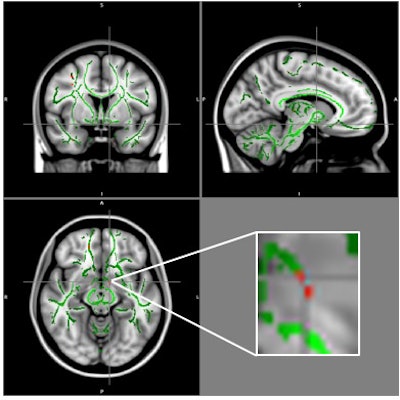

DTI-MRI measures fractional anisotropy -- that is, the microscopic motion, or anisotropy, of water molecules within and surrounding the brain's white-matter fibers. Low fractional anisotropy values suggest greater disruption within the white matter.

Bertolazzi and colleagues used DTI-MRI to image the brains of 59 obese adolescents who were between the ages of 11 and 18. They compared those images with results from a control group of 61 adolescents who were a healthy weight, matching the subjects by gender, age, socioeconomic classification, and education level.

The researchers found a loss of white-matter integrity in several brain regions in the obese patients compared to the healthy controls, including the amygdala, hippocampus, thalamus, cingulate gyrus, fornix, insula, putamen, orbital gyrus, and bilateral hypothalamus. Many of these regions help regulate appetite, impulse control, emotions, and reward and pleasure in eating, according to Bertolazzi's team.